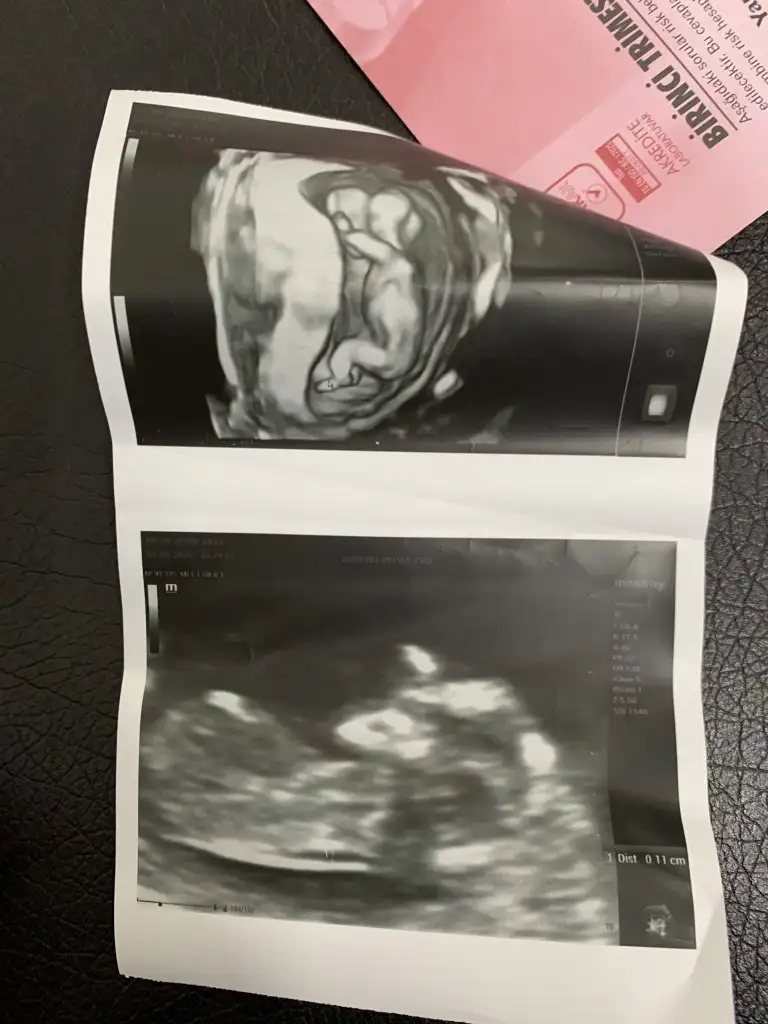

İkra meyra 12 haftalık ken tekrar foto atın demiştiniz burda 12+5 sizce cinsiyet ne ?

Eklentiler

• EDF88188-D37F-4A20-999C-B32BE1D02EF0.webp

EDF88188-D37F-4A20-999C-B32BE1D02EF0.webp

37 KB · Görüntüleme: 56